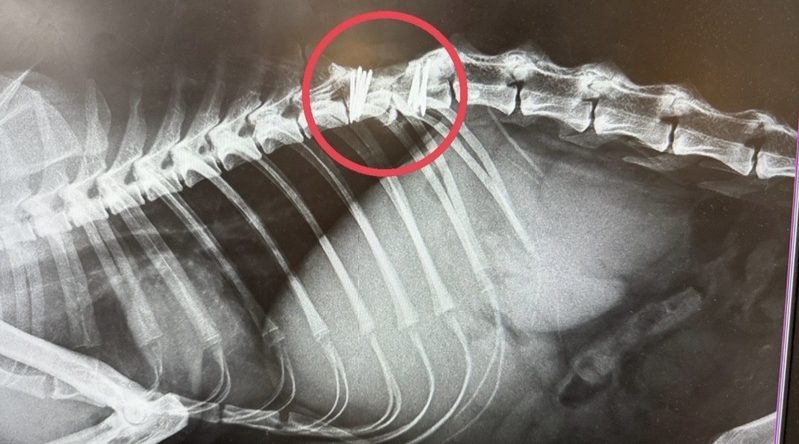

「2024年2月に大けがを負っているところを見つけたご近所の方と命のリレーで保護しました。手術を受けましたが、脊椎損傷の影響で下半身不随となり、これまで排尿補助や身の回りのケアを続けてきました。施設では、ほかの猫たちとも穏やかに過ごしていました」

「しかし、10月24日に体調を崩して入院。診断の結果、肝外胆管閉塞を発症しており、命の危険がある状態でした。

銀次郎くんは、自力で排尿ができないため、通常の圧迫排尿(下腹部を押して排尿を促す方法)が適用できず、カテーテル採尿(尿道カテーテルを使って膀胱から尿を排出する方法)を常時行っています。

この方法は膀胱炎を起こしやすく、今回も尿中に細菌が確認されました。さらに、ステロイド薬が使用できないため治療の選択肢が限られる中、厳しい状況が続きましたが、奇跡的に回復の兆しを見せ、現在は少しずつ元気を取り戻しています」

「皆さまからのご寄付は、今回の検査・治療費に活用させていただきました。

今後も注意が必要な状態ではありますが、これからも銀次郎くんに寄り添い、できる限りのサポートを続けていきたいと思います。

最期まで猫たちが安心して暮らせますように」